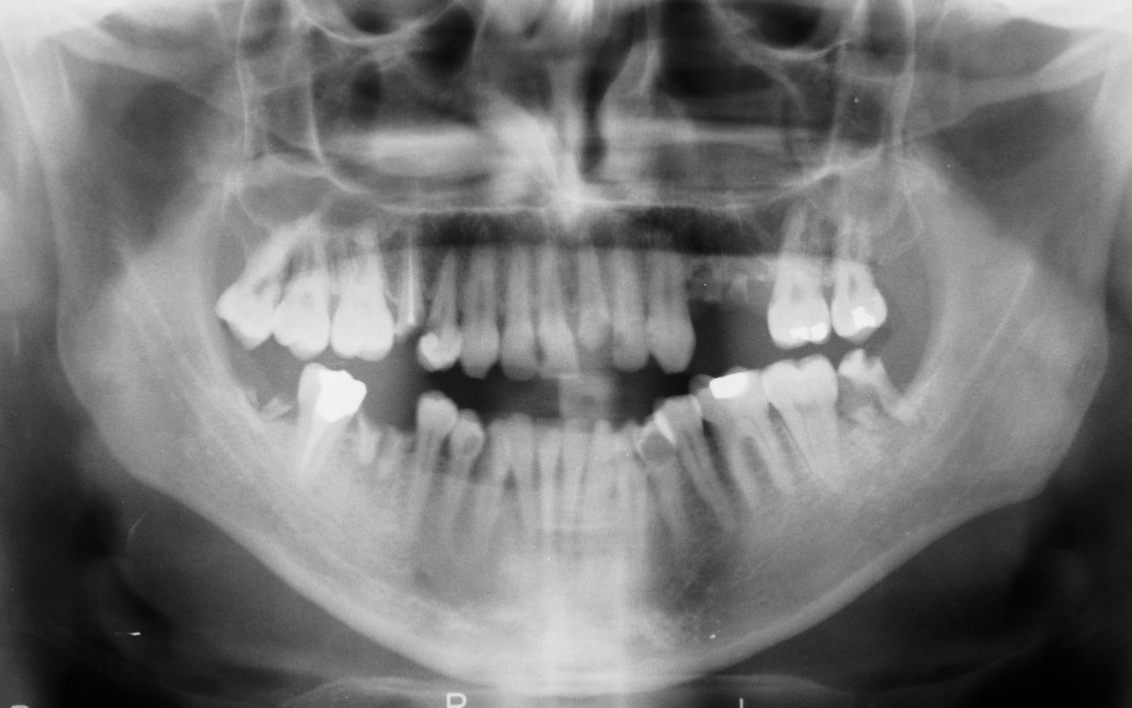

La caries es la enfermedad dental más común en todo el mundo y de acuerdo con los datos de la OMS, entre 60 y 90 por ciento de los niños y casi 100 por ciento de los adultos la padecen.

Se caracteriza por la destrucción de los tejidos de los dientes y se produce como consecuencia de los ácidos que genera la placa bacteriana a partir de los restos de comida que quedan en la boca. Esto lleva a la formación de cavidades y a la posterior inflamación del nervio de la pieza dental, ocasionando dolor.

Los dientes tienen naturalmente una cierta capacidad regenerativa: pueden producir una fina capa de dentina cuando la pulpa dental se queda expuesta.

La dentina, también llamada marfil o sustancia ebúrnea, es el tejido intermedio entre el esmalte dental, la capa externa más fuerte, y la pulpa, el tejido conectivo en el interior del diente.